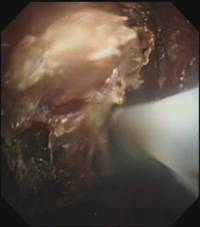

时间紧迫,每一秒都关乎生命,患者立即被送到内镜室,支气管镜检查的结果令人触目惊心:患者的总气管被痰痂、血痂、痰栓等物几乎完全堵死,仅残留一丝细小的通气通道,那是生命最后的脆弱纽带!

在紧张且充满紧迫感的抢救氛围中,呼吸介入团队成员默契配合,在支气管镜下使用异物钳夹取、超低温冷冻等方法清除异物。

随着每一次精准夹取和冷冻操作,顽固的异物被一点点从狭窄的气道内剥离出来,堆积在一旁的痰痂、血痂和痰栓逐渐增多,堆积起来的长度居然达到了惊人的18厘米。

当最后一块异物被取出,患者的气管终于露出了原来的“庐山真面目”: